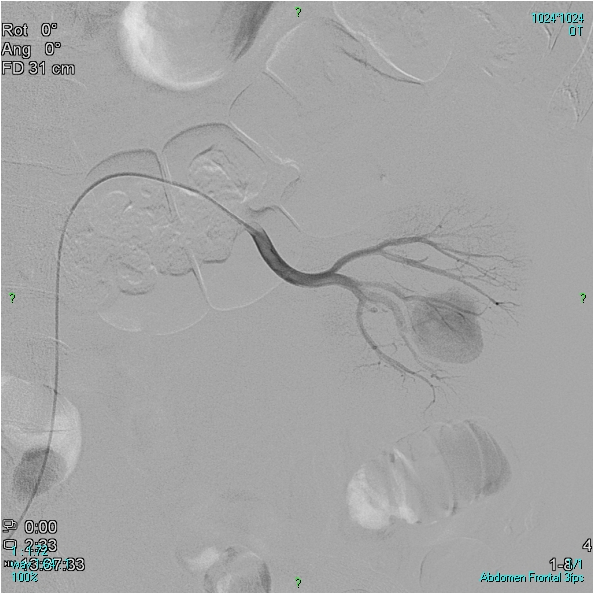

TACE is most often performed in the liver. The liver has dual arterial system, namely the hepatic arteries and the portal system. Normal liver tissue gains its arterial supply predominantly from the portal system, however, arterial supply for hepatocellular carcinoma (HCC) cells are mainly from the hepatic artery, which makes arterial TACE more effective. In order to prevent liver insufficiency, portal vein should be patent when TACE is indicated. Most frequent indication of TACE include irresecable liver tumor (HCC, colorectal carcinoma or other metastasis). The interventional radiological treatment is mostly palliative, increased survival time has been proved in case of HCC. Embolisation may be performed on any hypervascularised metastasis (e.g. neuroendocrine tumor, renal carcinoma metastasis).

Figure 8. A 55-year old male patient had resection of a 2,5 cm tumor from the left kidney. Macroscopic hematuria developed, which was repeatedly present. In the lower third of the left kidney, at the site of the former operation, contrast enhancement shows severe intraparenchymal bleeding (Panel A: catheter in the proximal position, Panel B: catheter in more distal position). The small arterial branches responsible for the bleeding were occluded using two metallic coils (Vortx-35, 3x7x67 mm, Boston Scientific) (Panel C). Urine was clear of blood within a few days, other treatment was not necessary. The only other altervative treatment would have been nephrectomy.